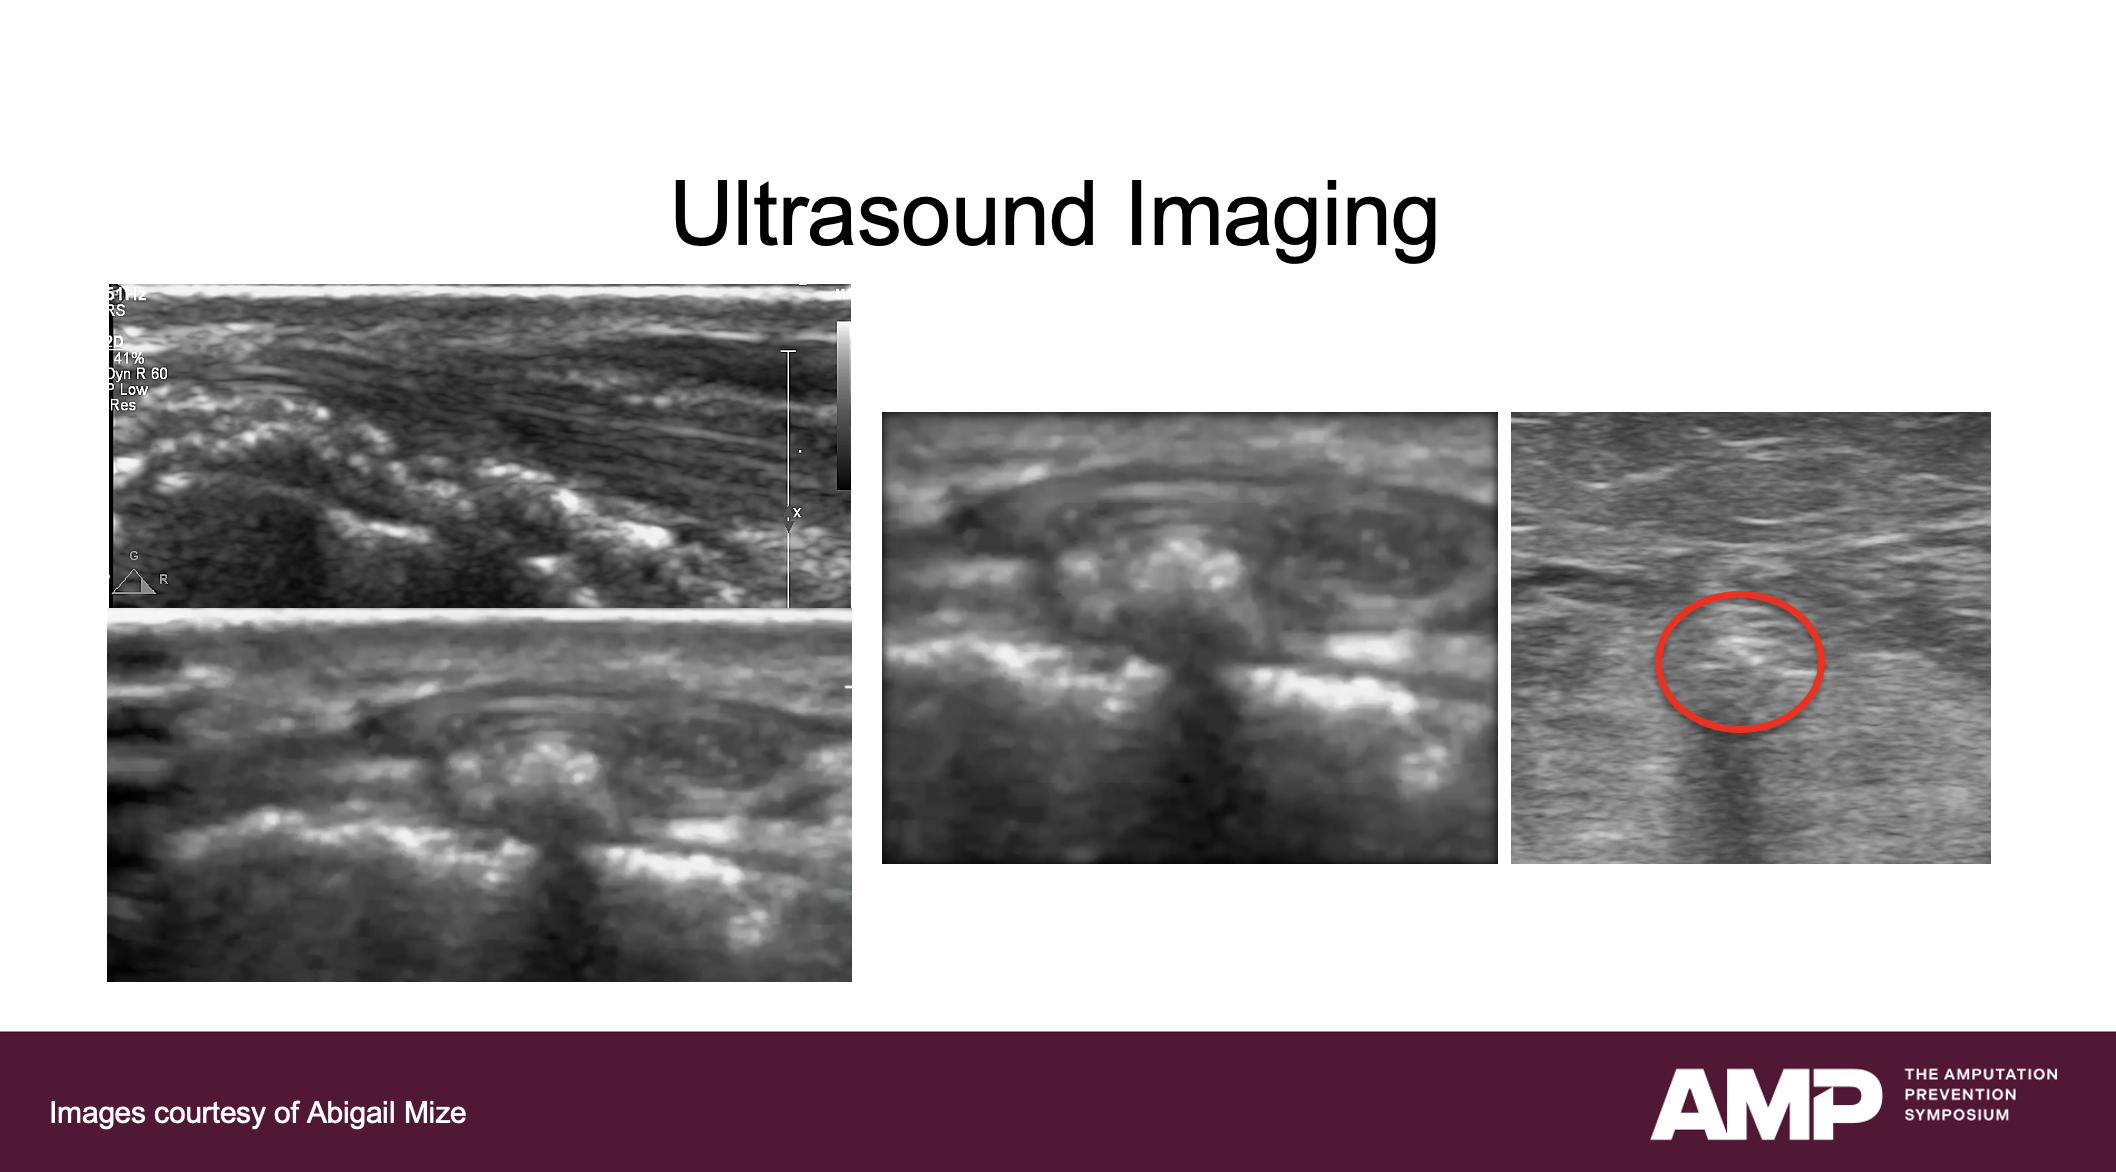

Ultrasound imaging characteristics came next; ultrasound findings for these patients may show vessels that are completely opacified with calcium or absent due to severe atresia. There is often no visible vessel lumen or discernible vessel layers, with significant acoustic shadowing present.